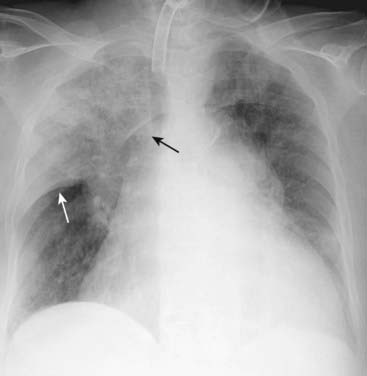

Figure 7-7 Primary tuberculosis.

There is prominence of the left hilum that is caused by left hilar adenopathy (solid white arrows). Unilateral hilar adenopathy may be the only manifestation of primary infection with Mycobacterium tuberculosis, especially in children. When it produces pneumonia, primary TB affects the upper lobes slightly more than the lower. It produces airspace disease that may be associated with ipsilateral hilar adenopathy (especially in children) and large, often unilateral, pleural effusions (especially in adults).

image

Figure 7-8 Post-primary tuberculosis (reactivation tuberculosis).

A cavitary pneumonia is present in both upper lobes (solid white arrows). Numerous lucencies (cavities) are seen throughout the airspace disease in the right upper lobe (solid black arrows). A cavitary upper lobe pneumonia is presumptively TB, until proven otherwise. In addition, airspace disease is seen in the lingula (dashed white arrow), another finding suggestive of TB, a disease which can spread via a transbronchial route to the opposite lower lobe or another lobe in the lung.